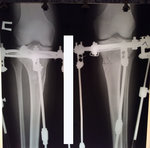

Ножки на сегодня.

Вложения

IMG-20170126-WA0032.jpg